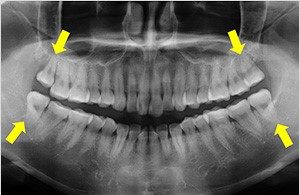

正式名称は「第三大臼歯」で、智歯(ちし)とも呼ばれています。永久歯の中で最後に発育し、生える時期が10代後半から20代前半であることから、親に知られることなく生えてくる歯、ということがその名前の由来だとも言われています。

1.親知らずが上下ともにきちんと生え、噛みあっており、また矯正をする予定がない

2.顎の骨の中に完全に埋まっていて、まわりの歯や骨に悪影響を与えることがないと考えられ、矯正をする予定がない